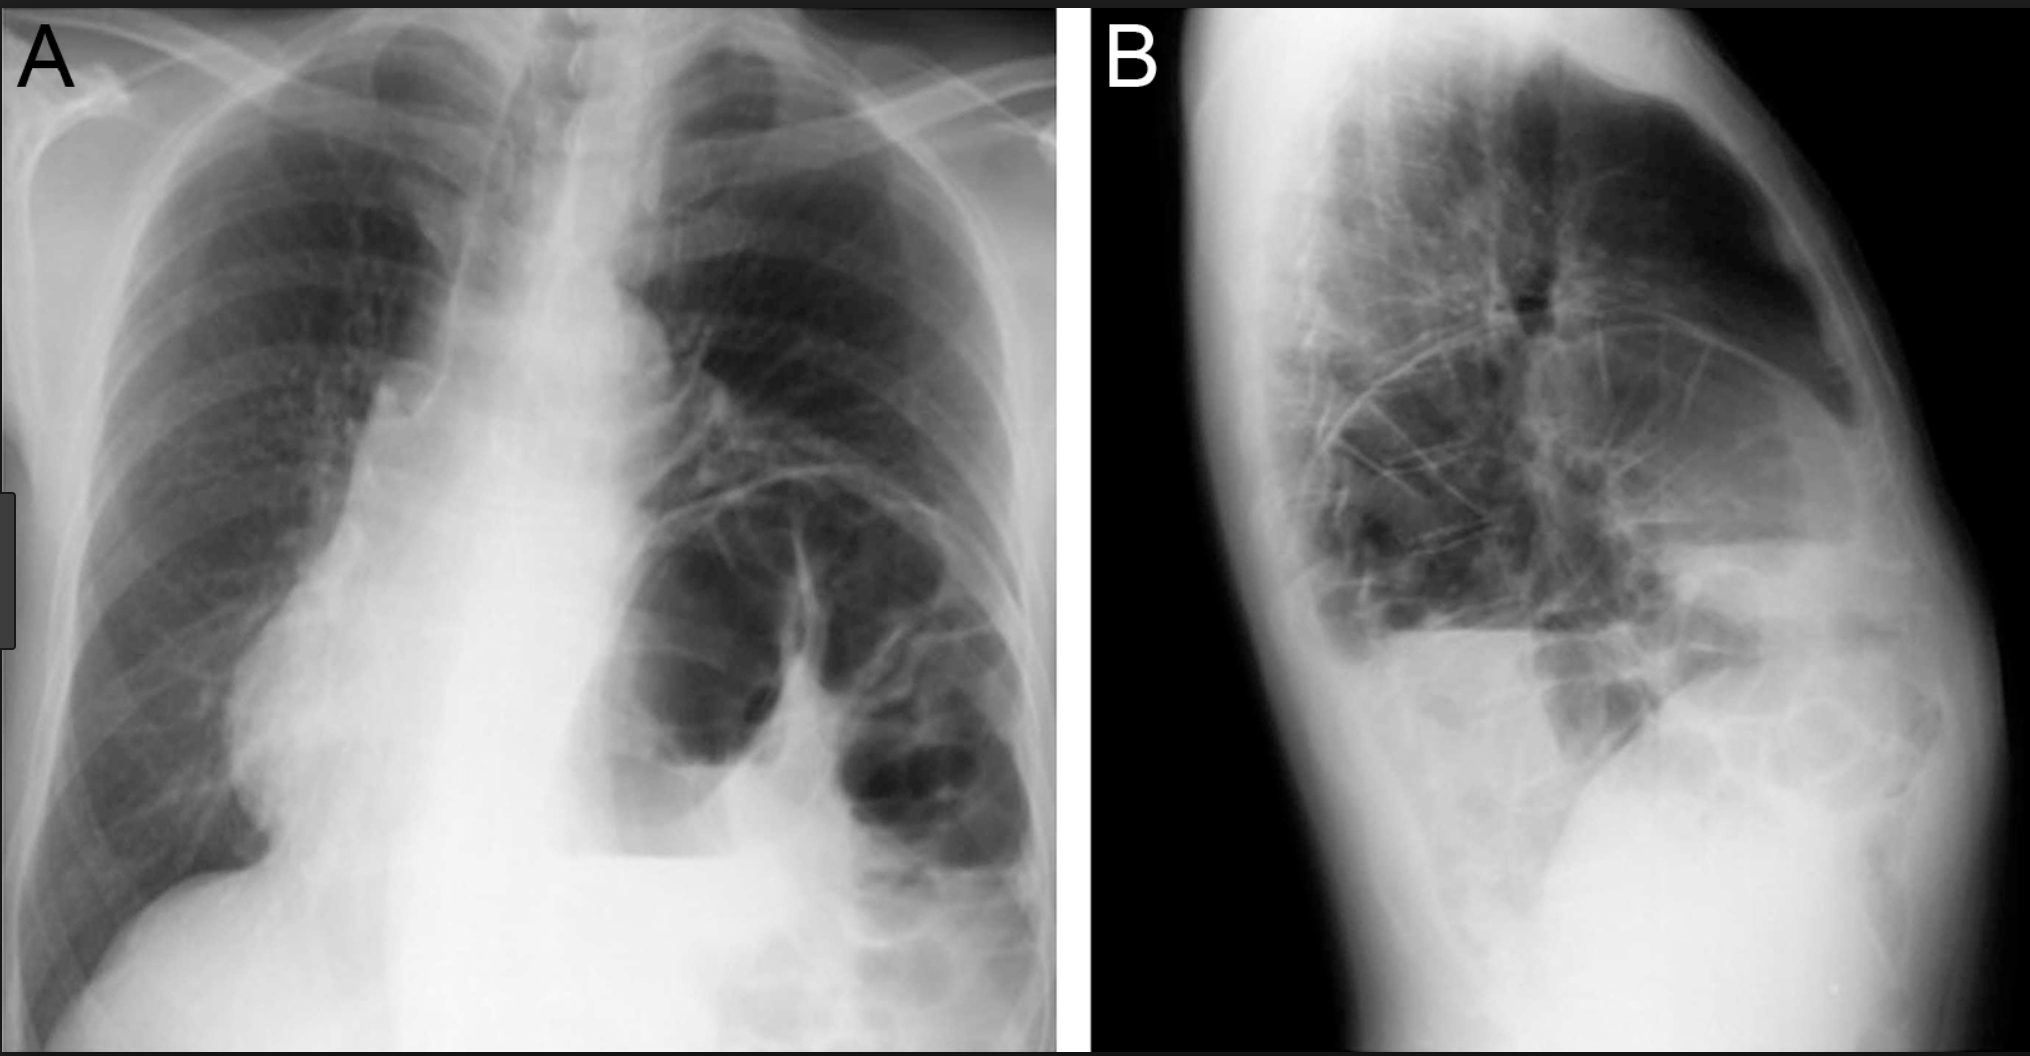

But where?

A: Minor Fissure

B: Major Fissure